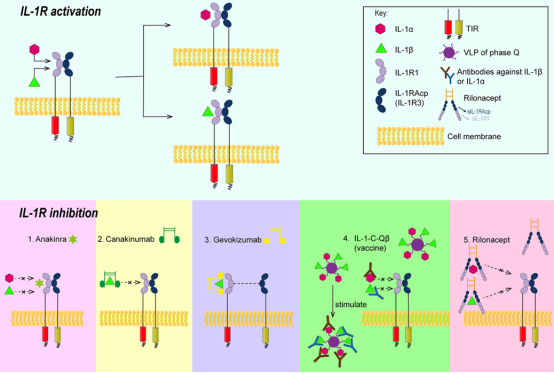

03. IL-1β 的信号通路

IL-1β的信号转导主要通过IL-1β受体相关激酶途径(IPAK途径)介导。首先IL-1β与IL-1R结合后,IL-1β,IL-1R I型(IL-1R1)和IL-1R辅助蛋白(IL-1Racp)形成异源三聚体;蛋白激酶4(IPAK4)和骨髓分化因子-88(MyD88)被活化,同时IL-1R活化蛋白激酶4自身磷酸化,IPAK1和IPAK2磷酸化,接着招募寡聚化肿瘤坏死因子受体相关因子(TRAF6),活化的TRAF6使有丝分裂原结合蛋白激酶MAPKKK家族活化;然后核内转录因子诱导激酶(NIK)被激活,被解除抑制的核转录因子(NF-κB)转入细胞核,调节相关基因的表达。

IL-1β信号通路被激活后,也会影响其他信号通路,如NF-κB、MAPKs、激活蛋白-1(AP-1)、JNK,p38 MAPK等,并进一步诱导相关基因表达,如IL-6,IL-8,MCP-1,COX-2,IL-1α,IL-1β等。

图1. IL-1β信号转导

Frontiers in Immunology DOI: (10.3389/fimmu.2020.589654)